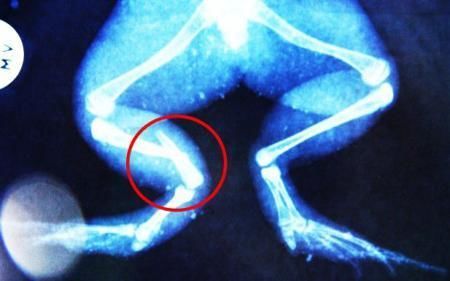

環(huán)球網(wǎng)4月2日?qǐng)?bào)道 據(jù)《每日郵報(bào)》報(bào)道,上個(gè)月,南非大牛蛙布魯萊的右小腿被鄰居家的一只狗咬到,導(dǎo)致粉碎性骨折,現(xiàn)在經(jīng)過(guò)2個(gè)小時(shí)的手術(shù),它的斷腿已經(jīng)被接上,它也因此成為有史以來(lái)第一只通過(guò)外科手術(shù)用鋼針接上斷腿的青蛙。

野生生物專家安妮經(jīng)常為學(xué)校寫(xiě)教材,她認(rèn)為這是人類第一次通過(guò)手術(shù)給一只青蛙接斷腿。在手術(shù)開(kāi)始階段,獸醫(yī)把少量給狗用的麻醉藥注入到這只青蛙體內(nèi),讓它失去知覺(jué)。然后他在布魯萊的斷腿上切開(kāi)一個(gè)小口,把一根小鋼針植入腿里。最后獸醫(yī)給它縫了9針,把切口縫合在一起。僅僅幾周后,布魯萊就能在安妮家附近活動(dòng)了。這只青蛙大約已有25歲,主要以嚙齒動(dòng)物、蛇和其他青蛙為食。布魯萊所屬的牛蛙種群正在不斷減小,目前只能在非洲南部的濕地里才能看到這種青蛙。